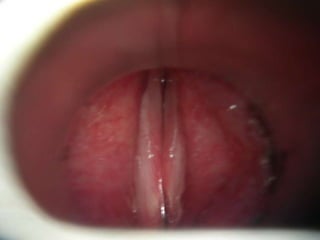

LARINGOSCOPIA (Directa o indirecta)

Indicaciones para laringoscopiaDisfonía de más de 2 a 3 semanas.Antecedente de tabaquismo y/o alcoholismo intensos.Síntomas asociados: disnea, disfagia, aspiración.Otros factores de riesgo para cáncer de laringe.

Espejo laríngeo

Endoscopio rígido